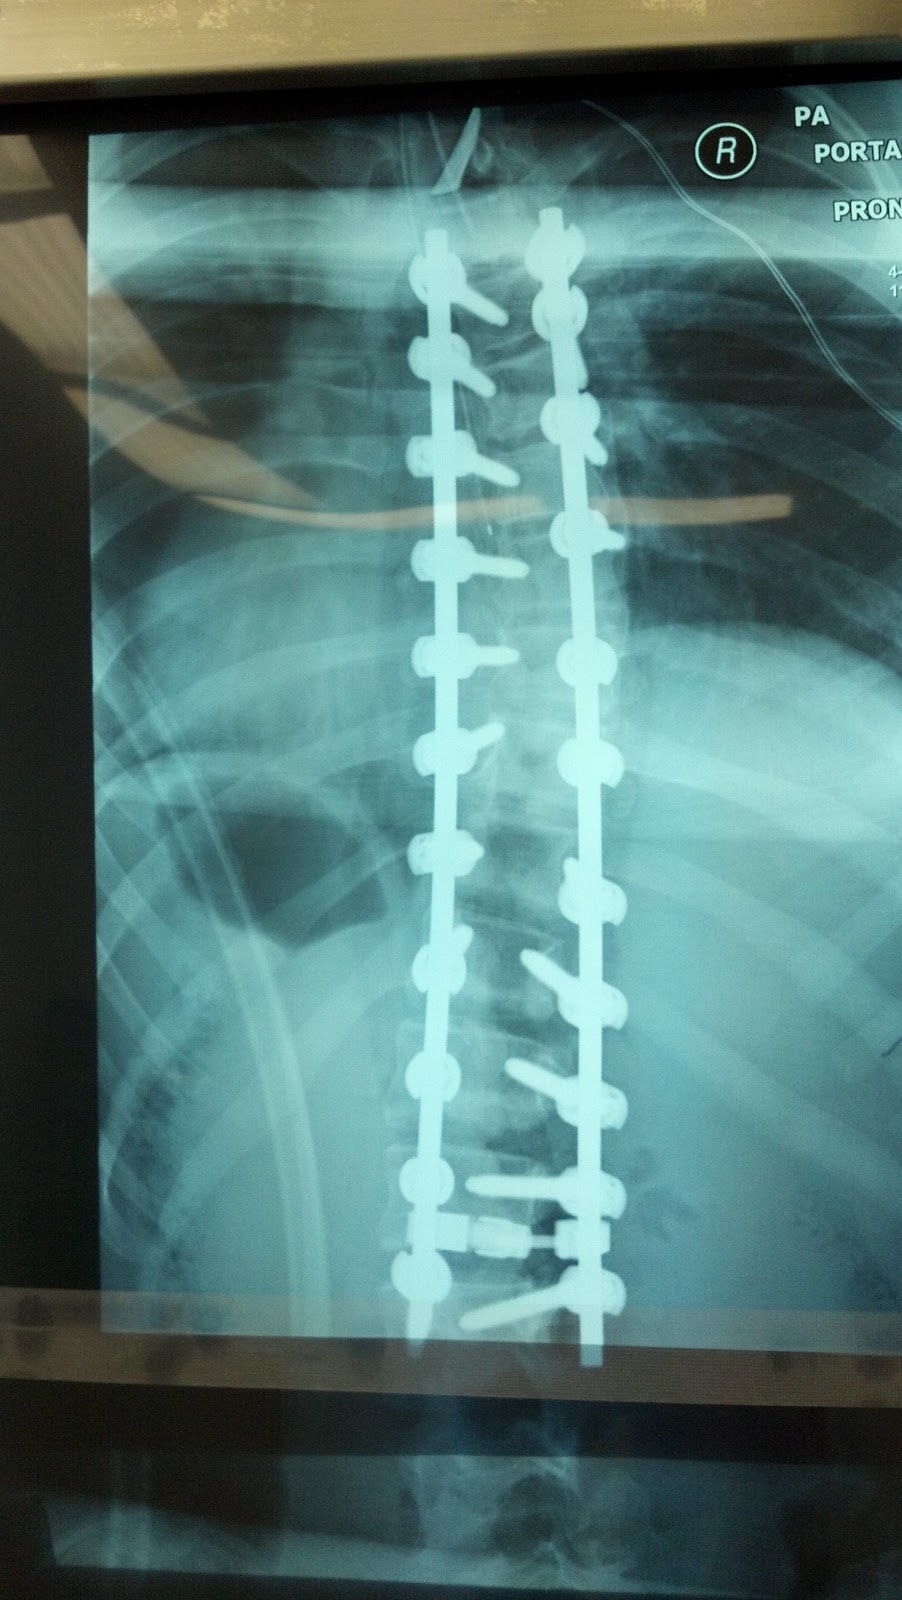

I just broke scrub on Julia's scoliosis surgery -- the 14 yo I talked about on this morning's blog with the large adolescent idiopathic scoliosis double curve. Her surgery this morning went great. Surgical time was 3 hours 50 minutes. EBL was 1000 cc, with 650 cc given back in cell saver, and no blood transfusions. Evoked potential monitoring was normal, and we got a really nice correction, even though her curves were very stiff!! Sometimes when patients are braced for a long time, I find their curves are stiffer. Fortunately we were able to overcome the stiffness by doing multiple osteotomies, and some additional manipulation using double rod technique and compression/distraction.

Just showed the films to Julia's mom and dad. They are so happy and wanted me to post this up to the blog so their family back in France can see the results. They are welcome to leave Julia "get well wishes through comments on the Blog.